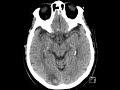

Intracranial Metastasis

Non contrast images of the head show hypoattenuation in the subcortical white matter of the right occipital lobe. Contrast enhanced images show avid enhancement of a nodular mass adjacent to this region of hypoattenuation which could have easily been confused for cortex on the noncontrast images. There is no significant mass effect or midline shift. This mass represents a metastasis in a patient with lung cancer. Lung cancer is the most common source of intracranial metastasis. These commonly are located at the gray-white matter junction in the brain. About half of intracranial mets are solitary.